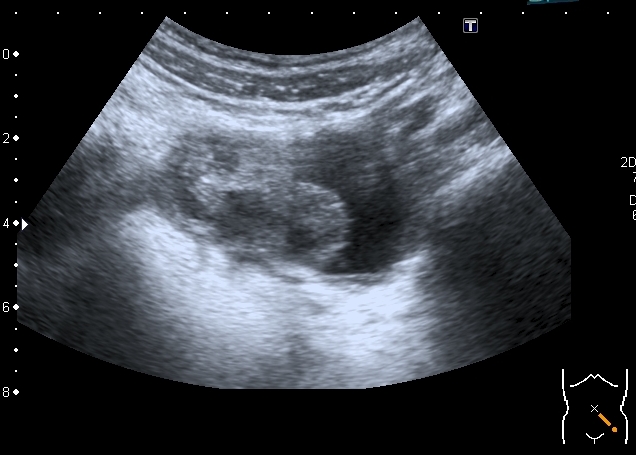

Правый яичник увеличен, с солидно - кистозными образованиями

Сходные по структуре образования в левом яичнике

Высказал предположение о множественных папиларных цистаденомах яичников. Хотелось бы узнать, насколько я прав.

Думаю, что на папиллярную цистаденому это похоже.

Никогда не встречал мультилокулярное и билатеральное поражение , но покопавшись в книгах, вычитал, что двухстороннее поражение составляет от 6 до 32% случаев. Очень подходит клиника - боли в животе, увеличение живота, дизурия. Дальнейший прогноз - 50% малигнизация.